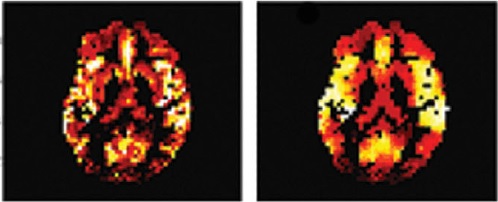

A robust method for correcting partial volume effect in ASL data

Description:CBF maps before and after applying PVC-mLTS